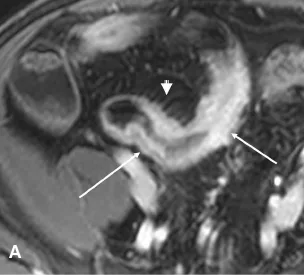

Son efficacité dans l’évaluation de l’inflammation est désormais bien explorée. Il est classiquement reconnu que les signes suivants témoignent de la présence d’une inflammation : l’épaississement de la paroi (supérieur à 6 mm), la prise de contraste marquée et en cocarde au temps parenchymateux, l’hypersignal en pondération T2, les ulcères et l’hyperhémie mésentérique [6-8]. Une restriction de la diffusion (hypersignal en diffusion et diminution de l’ADC) serait également un bon signe d’inflammation (Fig. 3) [9].

Figure 3. Patiente de 23 ans ayant une maladie de Crohn. Entéro-IRM montrant une atteinte iléale unique étendue sur 20 cm.

A. Séquence en pondération T1 après injection de gadolinium dans le plan axial montrant l’épaississement et la prise de contraste marquée avec aspect en cocarde de la paroi (flèches) ; signe du peigne en regard de l’anse pathologique (tête de flèche).